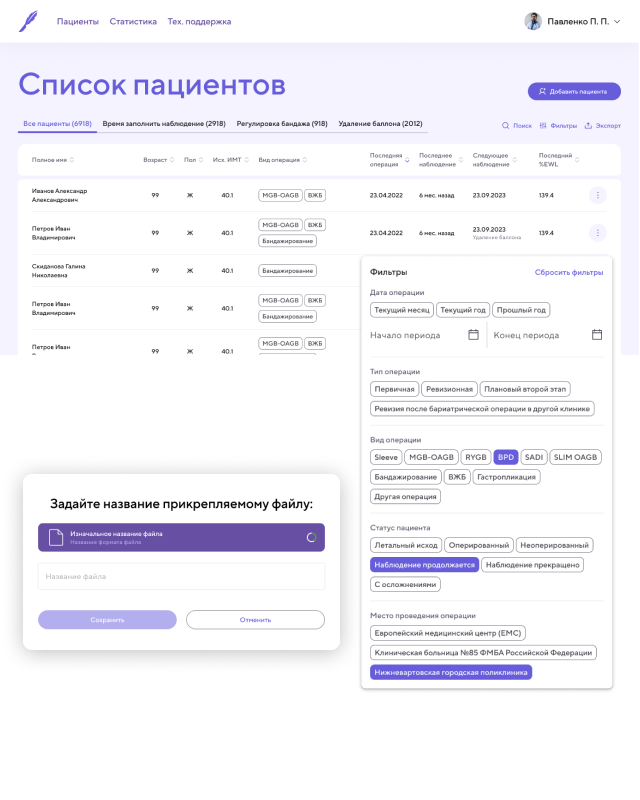

CRM Приложение [ 2022 ]

Работал над CRM-приложением для хирургической клиники по снижению лишнего веса, разработанным с использованием Pug, Vanilla.js и CSS. Приложение предназначено для ведения и учета пациентов, управления операциями и отслеживания результатов лечения.

В рамках проекта реализованы: авторизация и роли пользователей, создание и ведение карт пациентов, продвинутая фильтрация по различным параметрам, а также большие формы для создания операций и наблюдения за пациентами. Для визуализации результатов лечения использовались Chart.js, позволяя наглядно отображать статистику и эффективность применяемых методов.

Я работал над архитектурой интерфейса, реализацией ключевых функций, обеспечением удобного и логичного взаимодействия с данными, а также над оптимизацией форм и графиков для комфортной работы медицинского персонала. Приложение получилось функциональным, наглядным и удобным инструментом для управления пациентами и анализа результатов клиники.